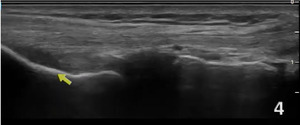

In the LAX view, depending on the probe width and size, one should start distally to visualize the hyperechoic reflection of the bony cortex of the fibular head distally and the cortex of the femoral epicondyle more proximally. If the depth is increased enough, you will also be able to visualize the bony reflection of the tibia directly below the fibular head. Usually, the LCL demonstrates a hyperechoic fibrillar pattern. The distal portion of the tendon may appear heterogeneous and thickened due to the bifurcating distal biceps femoris tendon that runs both superficial and deep to the LCL.9

Disruption of fibrillar pattern of the ligament in partial tears and ruptures.

Associated joint effusion, presenting as anechoic regions.